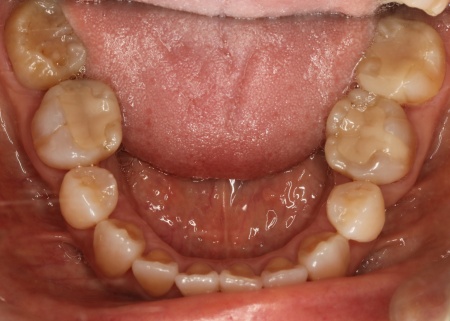

50代女性 インプラントアンカーを併用したワイヤー矯正で乱れた歯並びと噛み合わせを改善した症例

診断結果 拝見したところ、上下の歯がデコボコに乱れて生えていました。

歯の大きさに対して顎が小さいため、歯が正常に並びきらず、全体的な噛み合わせのバランスも崩れています。

噛み合わせを詳しく検査したところ、実際にしっかりと噛み合っているのは一部の歯だけで、このまま放置すると特定の歯に負担が集中し、将来的に痛みや違和感が生じるおそれがあります。

また、銀歯が装着されている右下奥歯は以前神経を抜く治療がされていましたが、現在は歯の具合が良好とはいえず、温存が難しい状態です。